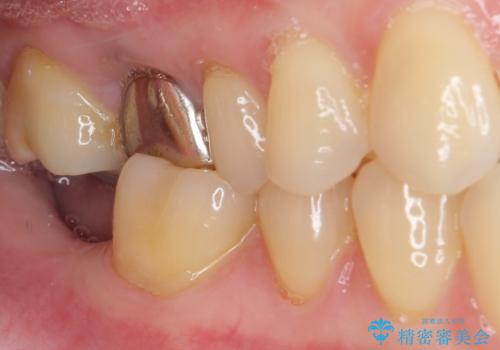

抜歯されたままの奥歯 ストローマンインプラントによる欠損補綴治療

- 抜歯してから放置されている右下の奥歯へのインプラント治療を希望して来院された患者様です。

世界中で高い信頼を得ているストローマンインプラントを用いて治療を行うこととしました。

ストローマン社のSLActiveというインプラントを使用し、インプラント埋入からクラウンが装着されるまで3ヶ月弱という短期間で終えることができました。